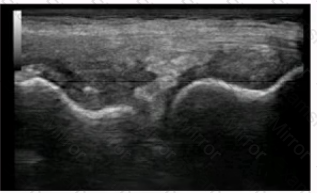

This ultrasound image from a 60-year-old woman with knee pain is MOST suggestive of which of the following?

What is the MAIN pathologic finding shown in this ultrasound image?